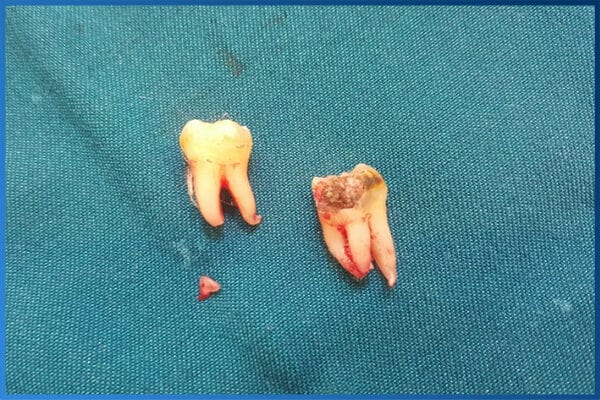

- Mọc lệch, mọc ngầm gây chèn ép/tiêu chân răng số 7, chen chúc khớp cắn.

- Sâu răng, viêm nha chu vùng răng khôn; phát hiện u nang quanh thân răng.

| Tiểu phẫu răng khôn mọc kẹt/ngầm | 1.500.000 – 3.000.000 |